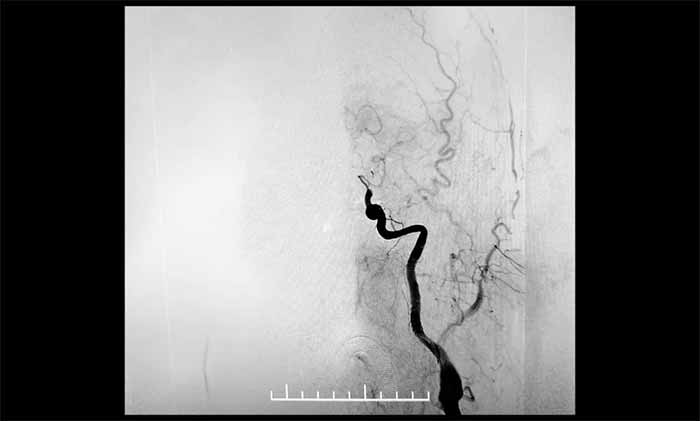

醫(yī)院立即啟動(dòng)卒中應(yīng)急預(yù)案。影像檢查提示:左側(cè)頸內(nèi)動(dòng)脈、大腦中動(dòng)脈、大腦前動(dòng)脈A1段未見(jiàn)顯影,考慮急性閉塞——范圍更廣,病情危急。

▲ DSA顯示,左頸內(nèi)動(dòng)脈C7段閉塞